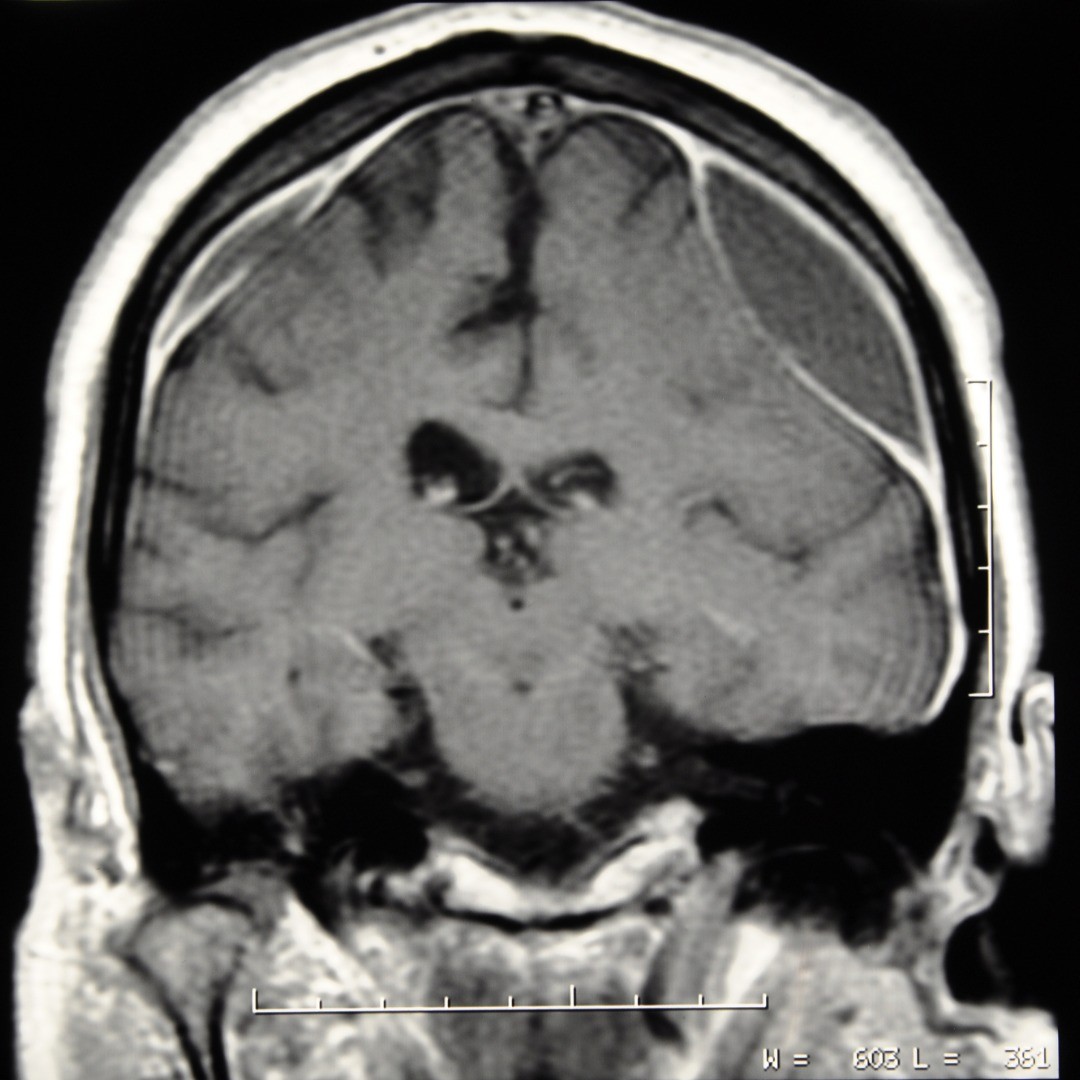

A craniotomy for subdural hematoma allows a neurosurgeon access through the skull via a small opening for the extraction of a blood clot on the exterior of the brain. These blood clots (hematomas) are underneath (sub) the dura mater (dural) or outer covering of the brain and occur when the blood vessels that traverse the space are ruptured.

The symptoms for a subdural hematoma resulting from a head injury can be immediate, known as an acute subdural hematoma, or can develop over time after an injury—sometimes even several weeks, called a chronic subdural hematoma. Symptoms can include: